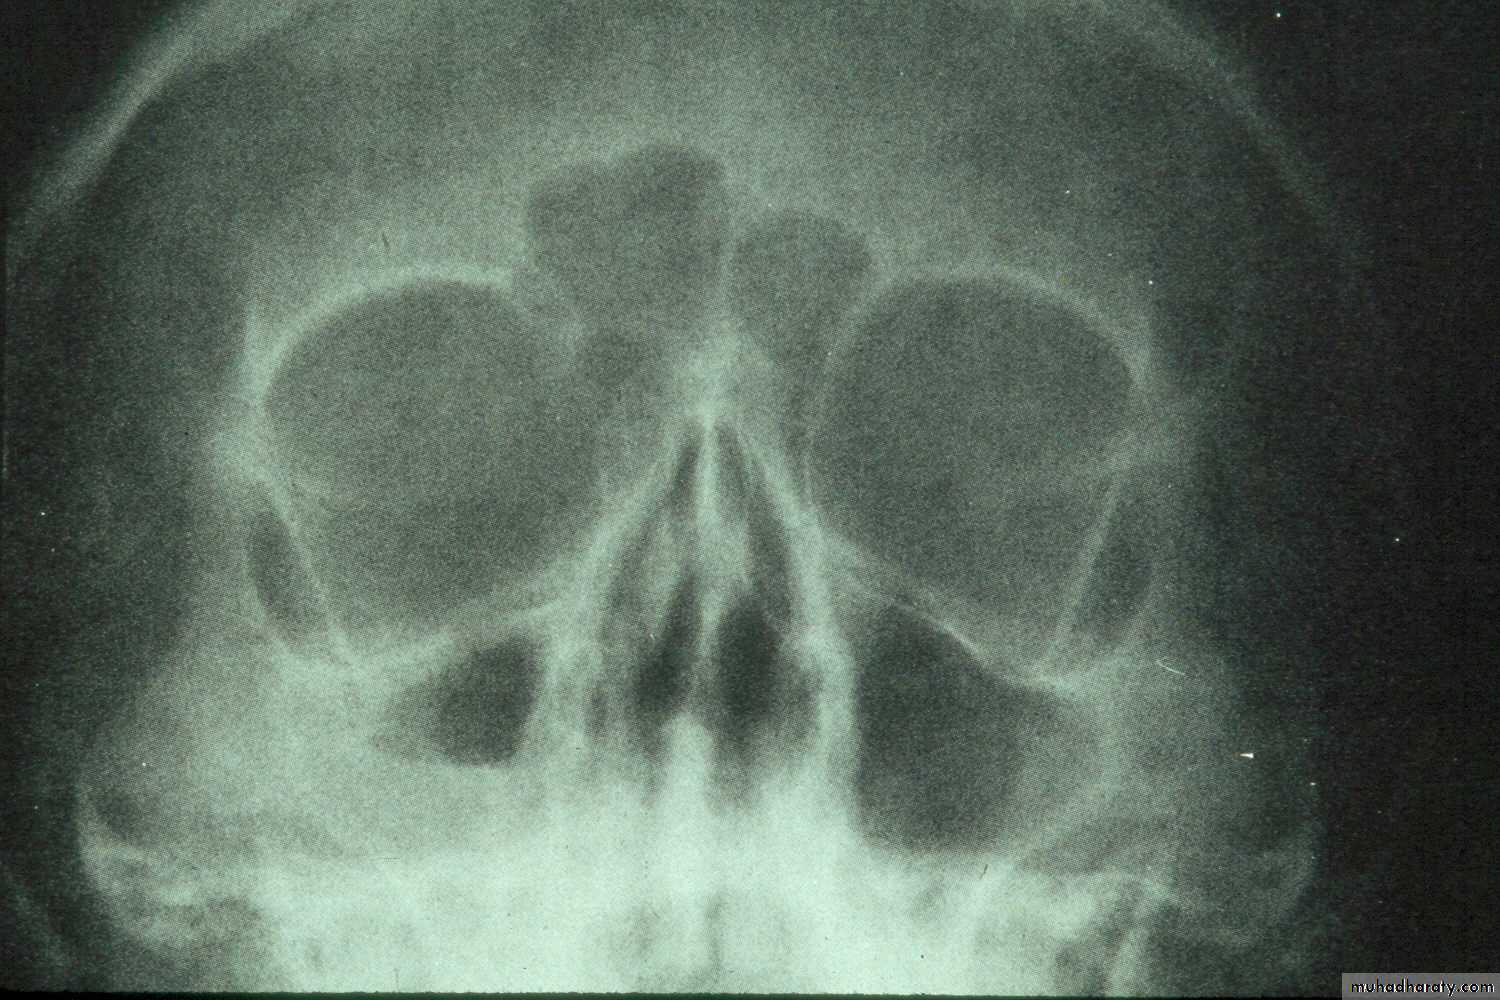

• Extraoral views:• Occipitomental View (15° OM): it’s called Water’s view. The presence of pus will produce a horizontal fluid level in this view; provided that there is air above it. As a measure of confirmation of the diagnosis, the view is repeated with the head tilted toward the side of pathology. The fluid level remains horizontal.

Radiographic signs of sinus pathology :

Air fluid levels

Partial or complete opacification

Bony wall displacement

4 mm or more of mucosal wall thickening

Water’s view showing air-fluid level in right maxillary sinus and mucosal thickening in left maxillary sinus